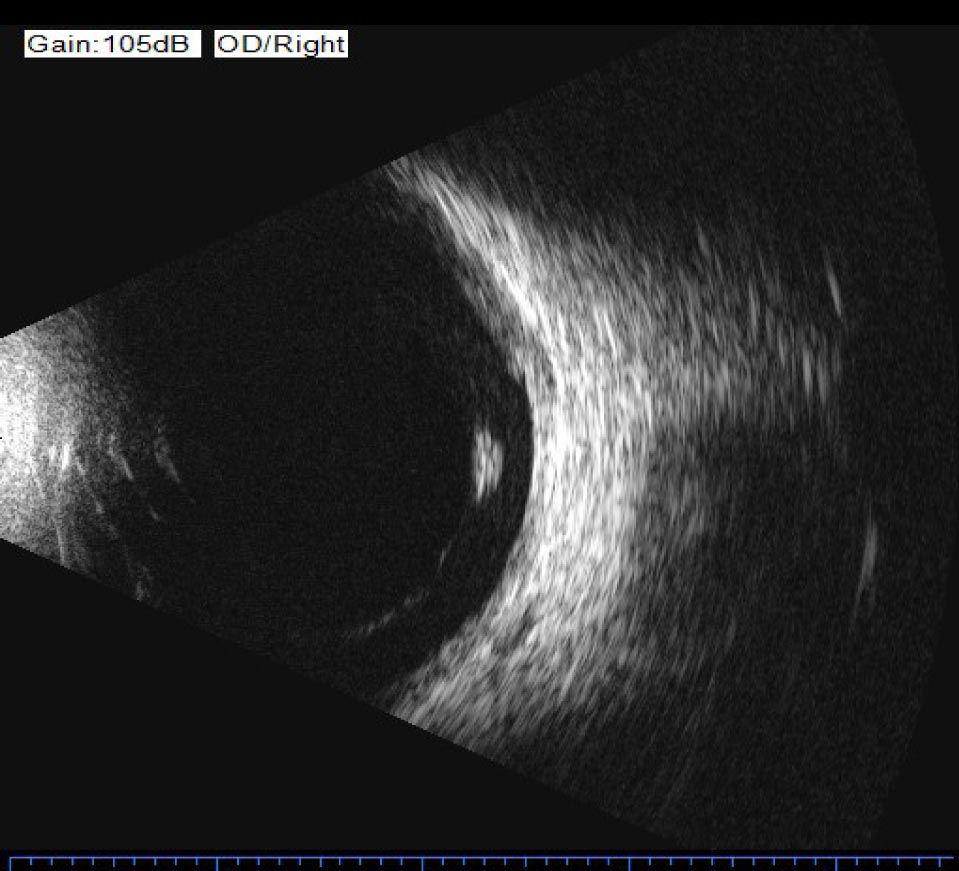

La ecografía ocular utiliza ultrasonidos de alta frecuencia (10–20 MHz) para obtener imágenes del interior del ojo y la órbita. El modo A (unidimensional) mide distancias con alta precisión para biometría. El modo B (bidimensional) genera imágenes en tiempo real del polo posterior y la órbita.

Es fundamental cuando los medios oculares están opacos (catarata densa, hemorragia vítrea) y no es posible visualizar el fondo de ojo. Permite detectar desprendimiento de retina, tumores intraoculares, cuerpos extraños y patología orbitaria.

Ecografía ocular modo B – Centro de Ojos Liniers

Cuando la hemorragia vítrea o la catarata densa impiden ver el fondo de ojo, la ecografía en modo B permite evaluar si la retina está aplicada y descartar patología grave.